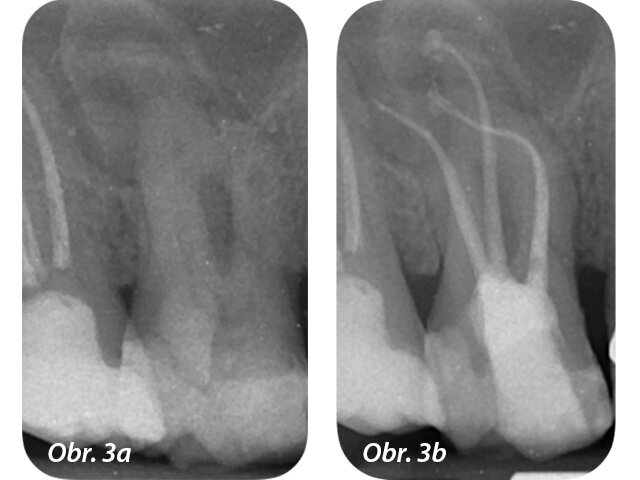

Dosažení co nejlepšího opracování a vyčištění systému kořenových kanálků je náročnější v případech léčby zahnutých kanálků. Jejich anatomie může představovat problém pro průnik nástrojů a může snížit jejich efektivitu. Vývoj nástrojů používaných na tvarování systému kanálků přinesl s příchodem strojových nikltitanových (NiTi) nástrojů vylepšení v dosažení čistoty stěn kořenových kanálků oproti manuálním nástrojům, avšak vysoké procento povrchů kanálků zůstává stále nedotčeno.Mechanické opracování navíc není schopno odstranit všechen smear layer na povrchu stěn kořene, a to především v apikální třetině nebo u případů se složitou anatomií (obr. 3a–d).

Srovnávací studie Li a kol. jasně uvádí, jak je důležité si uvědomit, že žádný plnicí materiál nebo technika nemůže kompenzovat nevhodnou asepsi a dezinfekční postupy.Z tohoto důvodu musí být dosažení dobré dezinfekce systému kořenových kanálků hlavním cílem zubních lékařů, a to především u zahnutých kanálků.

Anatomie zubů způsobuje, že opracování kanálků může být velmi nevypočitatelné a mechanickou preparací nelze dosáhnout všech oblastí kořene. Také výplachy mohou jen obtížně penetrovat do úzkých prostor a obtíže s dosažením nejapikálnějších oblastí kanálku velkými objemy výplachu mohou vyústit v nižší výkon během čištění.Nejčastější metodou k umístění výplachového roztoku do opracovaného kanálku, která odpovídá všeobecným doporučením k maximalizaci výplachové efektivity a vyhnutí se přetlačení výplachu do periapikálních tkání, je pomocí stříkačky a jehly.Většina výplachových jehel je vyráběna z oceli a tento materiál není schopen přizpůsobit se anatomii kořenového kanálku, obzvlášť v přítomnosti jeho ohybů. Následně se tedy jehla zastaví o jednu ze stěn kanálku, což snižuje míru čerstvého výplachu, který dosáhne apikální třetiny a zvyšuje střihové napětí na stěnu kanálku.